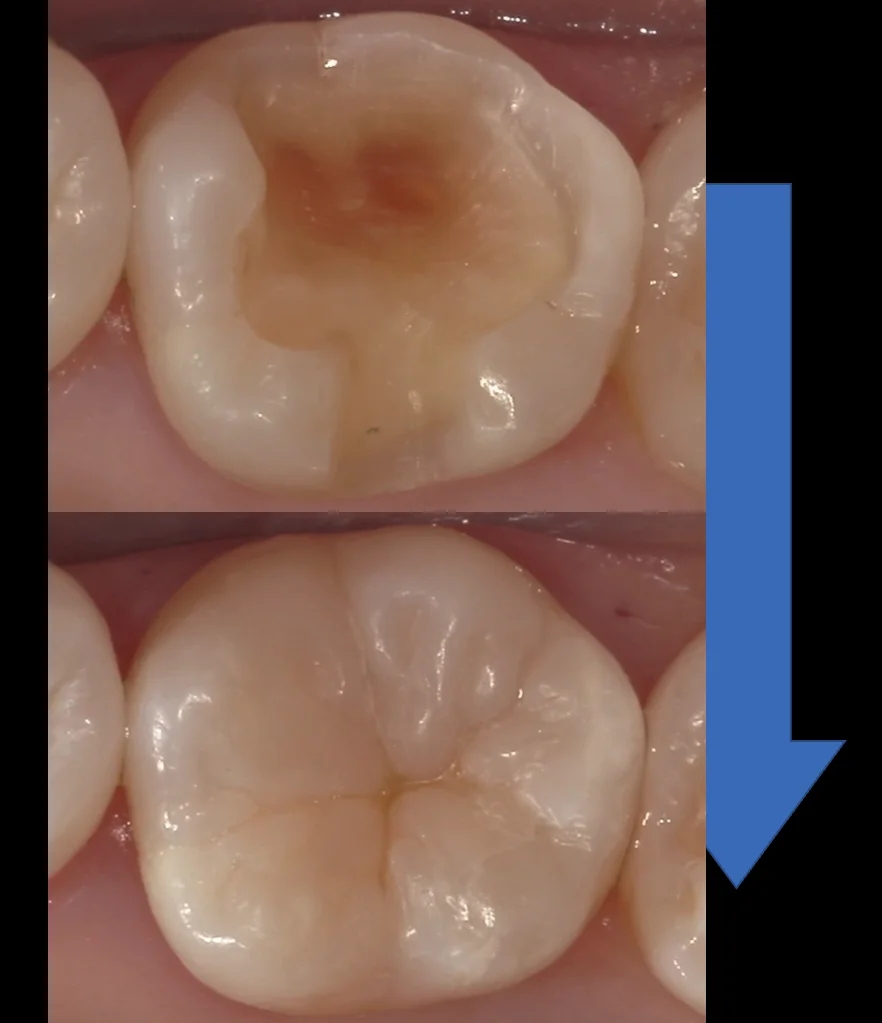

2人目はこちらの、北陸の方から車で5時間かけて通院してくださった方です。

色が分かりづらいと思いますので、もし気になるならリンク先から飛んでみてください。

非常に虫歯が大きくほとんど歯が残っていないような状況でした。

その1年予後の写真です。

特に大きな変化は起こっていないのがわかるかと思います。